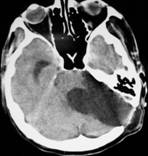

Extensive microscopic tumor resection was performed in 5 (71.42%) cases; diagnosis was confirmed by histopathology in all cases. There were no deaths and the tumors were histological benign (Fig.1). Partial tumor removal was performed for 2 cystic tumors were the arachnoidal plane was poorly defined, with severe adherences to brainstem and facial nerve, extensive bleeding and cerebellar edema.

A B C

D E F G

Fig. 1 Preoperative cerebral CT showing giant VS (51 mm) with obstructive hydrocephalus (A-C); postoperative cerebral CT after 1 year follow-up showing complete resection (D, E); another case with giant VS (57 mm) showing pre and postoperative CT